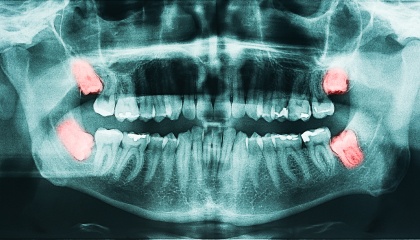

During your initial visit, we'll delve into your medical history and have a thorough discussion about the wisdom teeth removal process. We'll take x-rays to assess the position and condition of your wisdom teeth, allowing us to create a personalized treatment plan tailored to your specific needs. This plan will outline the costs, timeline, and steps involved in the procedure. We also encourage you to ask any questions you may have; we're here to address any concerns you might have about the procedure.

The decision to remove wisdom teeth depends on several factors and is usually made after a comprehensive examination by your dentist at Today Dental. Wisdom teeth, also known as third molars, may need removal if they cause problems like:

- - Impaction: Stuck in the jawbone and unable to erupt properly.

- - Crowding: Cause other teeth to shift or become misaligned.

- - Pain or pressure: Cause discomfort or pressure in the jaw.

- - Infection: Become infected due to difficulty cleaning them properly.

- - Damage to nearby teeth: Damage or harm surrounding teeth.